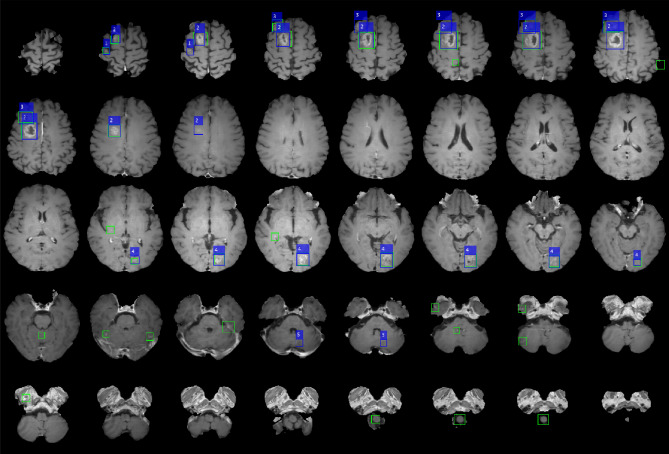

An example of a patient with five metastatic lesions of non-small cell lung carcinoma is shown in Fig. 1. Table 1 shows the performance of the five-fold cross-validation of DLA. The overall performance was 87.95%, 24.82%, 19.35%, 14.48, and 18.40 for the sensitivity, precision, F1-Score, and false positive average (FPavg) for the training cohort and normal individual dataset, respectively. For five-fold cross validation, the maximum and minimum sensitivities were 97.44% (DataSet5) and 81.82% (DataSet3), respectively, and the maximum and minimum FPavg were 21.57 (Model 2) and 7.27 (Model 3), respectively. Figure 2 shows examples of false positives from the DLA. The regions where false positives were mainly found were insufficiently suppressed in the vessel region. In addition, false positives were often observed in the choroid plexus, medulla oblongata, and basilar artery.

Figure 1.

Example of a case of a 67-year-old male patient with five brain metastases. (Origin of metastases is non-small cell lung carcinoma) The numbers 1–5 are displayed at each lesion. Blue boxes show the label that the lesion placed more than two adjacent slices and green boxes show the prediction result by deep learning algorithm. This figure was generated by MATLAB (MathWorks, R2020b, Natick, MA, USA).